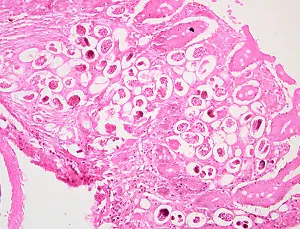

In humans, Angiostrongylus eggs and larvae remain sequestered in tissues and do not appear to be excreted in stool. A. costaricensis infections are predominantly abdominal; both eggs and larvae (occasionally adult worms) can be identified in biopsy or surgical specimens of intestinal tissue, where the eggs and larvae typically are engulfed in giant cells and/or granulomas.

The larvae of A. costaricensis in tissue sections need to be distinguished from larvae of Strongyloides . A. costaricensis first-stage (L1) larvae tend to be slightly smaller in diameter than S. stercoralis third-stage (L3) larvae and have single lateral alae, whereas S. stercoraliss L3 larvae have minute double lateral alae. The alae can be difficult to discern in most histologic sections. However, the presence of granulomas containing thin-shelled eggs and/or larvae generally serves to distinguish A. costaricensis infections from Strongyloides infections.

Diagnosis of abdominal angiostrongyliasis (A. costaricensis infection) is based on finding eggs, larvae, or adult worms in histologic sections. The patient’s travel/exposure history may prompt consideration of the diagnosis.